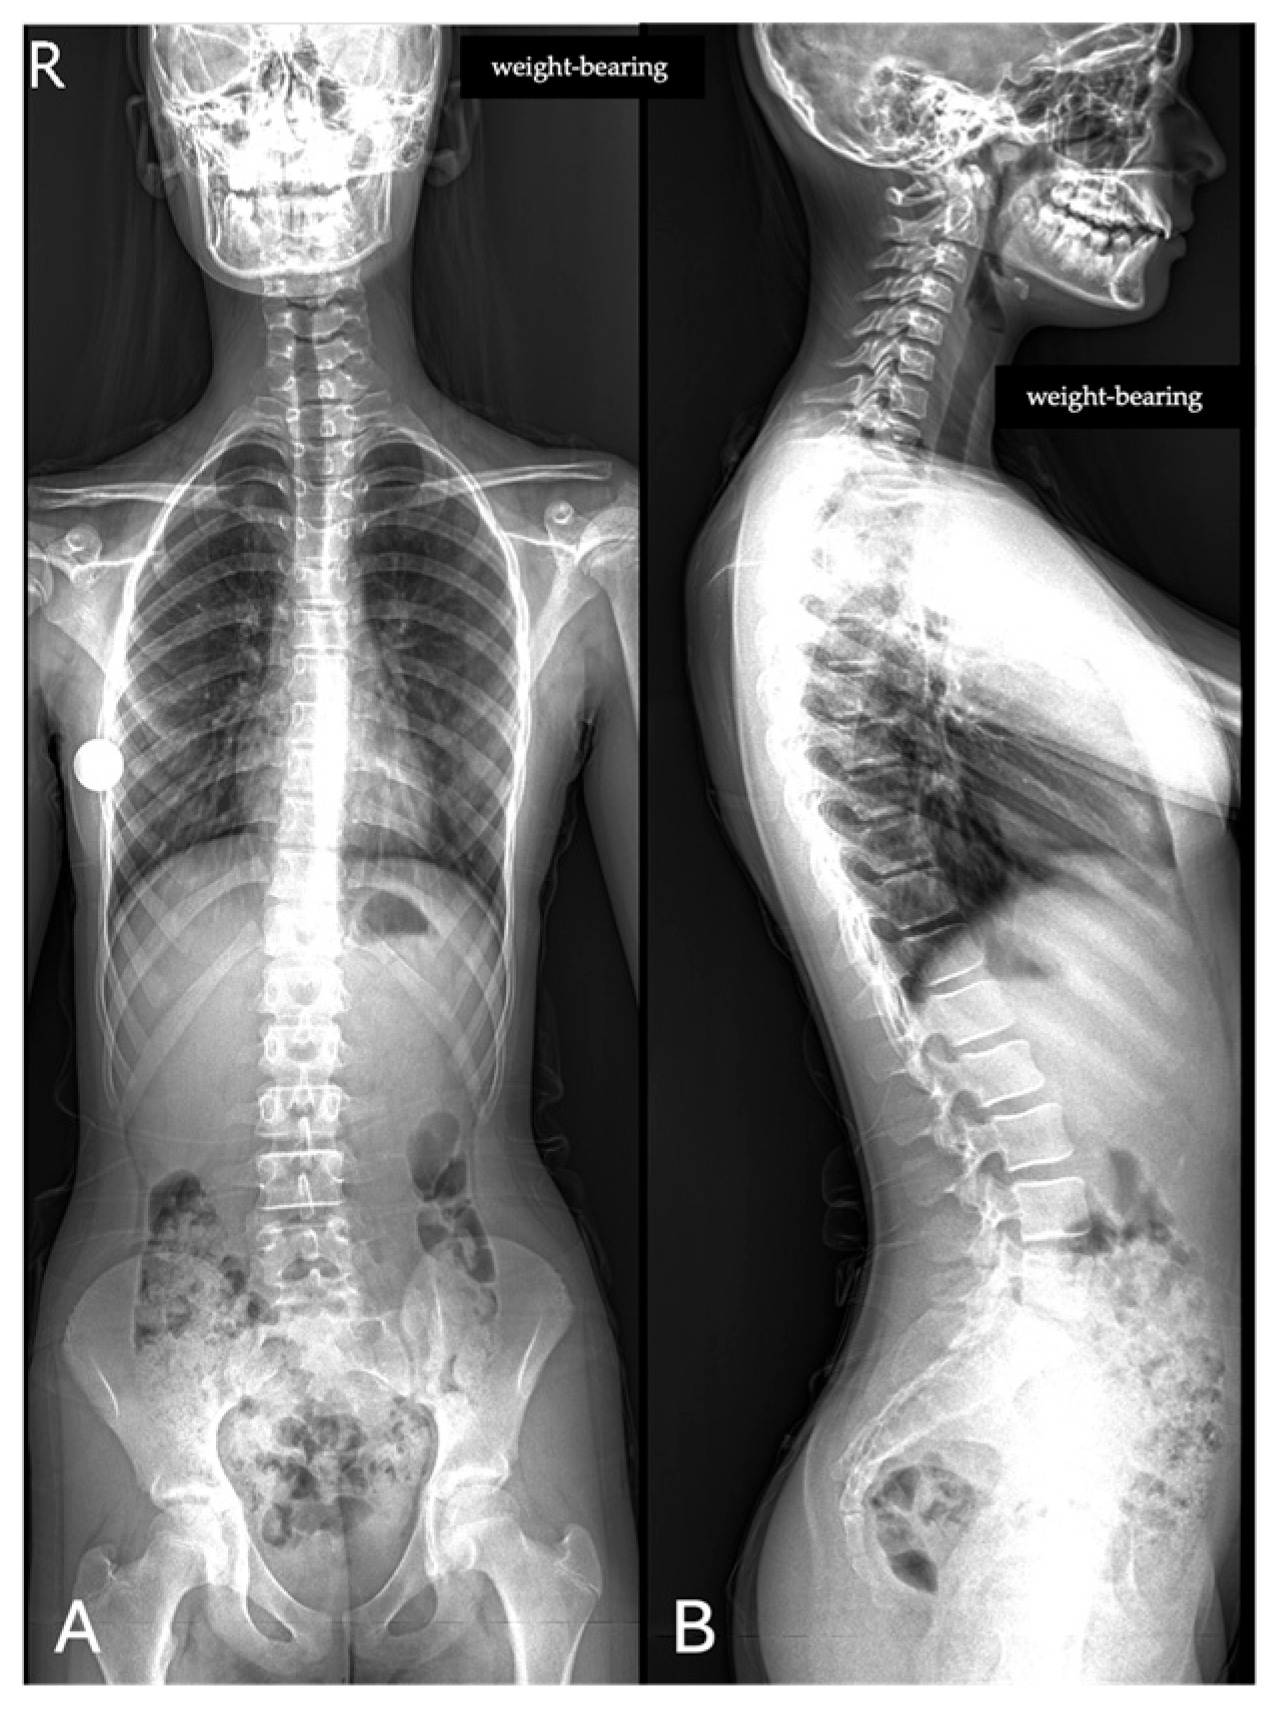

The concordance between measurements by the experienced radiologist, radiology resident, and AI demonstrated a high level of agreement across all parameters, with CCC values exceeding 0.9 in most cases (Figure 3 and Figure 4).

For the Cobb angle, the AI achieved a lower MAE (0.577) compared to the resident (0.632), indicating slightly greater accuracy. For thoracic kyphosis, the resident exhibited a lower MAE (2.375) compared to the AI (2.464), suggesting better agreement with the expert in this measurement. In the case of lumbar lordosis, the AI demonstrated superior accuracy with a lower MAE (1.395) compared to the resident (1.902). Conversely, for pelvic obliquity, the resident achieved a lower MAE (0.296) compared to the AI (0.475) (Table 2). The inter-observer agreement between the experienced radiologist and the resident was excellent for all parameters (ICC range 0.905–0.996). When including the AI software as a third reader, the overall concordance remained excellent (ICC range 0.931–0.996). In addition, intra-observer reproducibility was also excellent across all parameters (ICC > 0.90).

Figure 4. Sagittal spine image analysis in the same patient. (A) Automated measurements of thoracic kyphosis (T4–T12) and lumbar lordosis (L1–S1); (B) manual measurements performed by a radiologist.